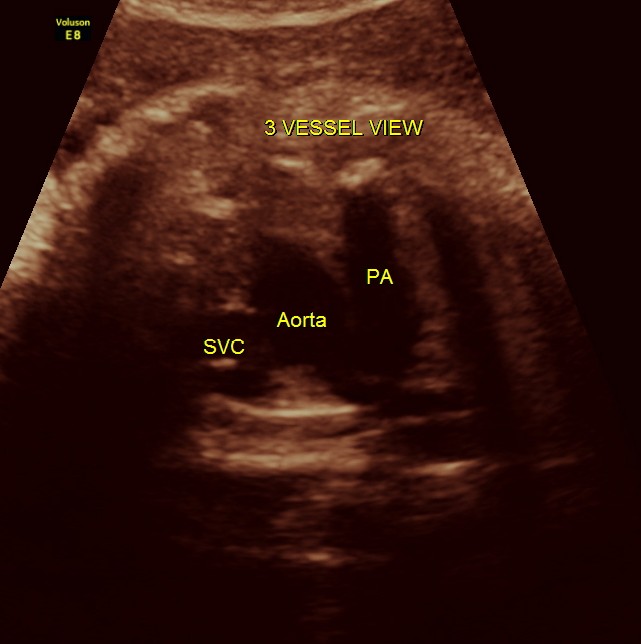

THIS FETUS HAD SEVERE FETAL ANEMIA WITH CARDIAC FAILURE LEADING TO CARDIOMEGALY WITH MITRAL, TRICUSPID AND PULMONARY REGURGITATION .NO OTHER OBVIOUS CARDIAC ANOMALY WAS MADE OUT . THE VENO ATRIAL , ATRIO VENTRICULAR AND VENTRICULO ARTERIAL CONCORDANCE APPEARED TO BE NORMAL; NO SEPTAL DEFECT WAS MADE OUT.